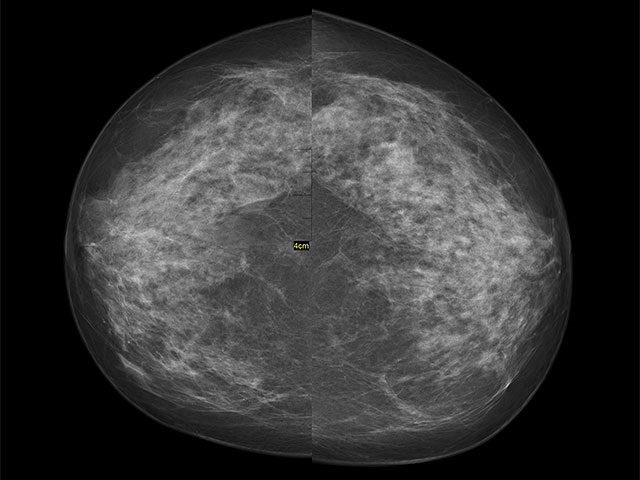

Отсутствие первой маммографии повышает риск смертности от рака молочной железы

Женщины, которые не проходят первую маммографию, имеют повышенный риск обнаружения рака молочной железы на более поздних стадиях.

Женщины, которые не проходят первую маммографию, сталкиваются с повышенным риском обнаружения рака молочной железы на поздней стадии и более высокой вероятностью летального исхода. К такому выводу пришли ученые Каролинского института, результаты их исследования опубликованы в научном журнале BMJ.